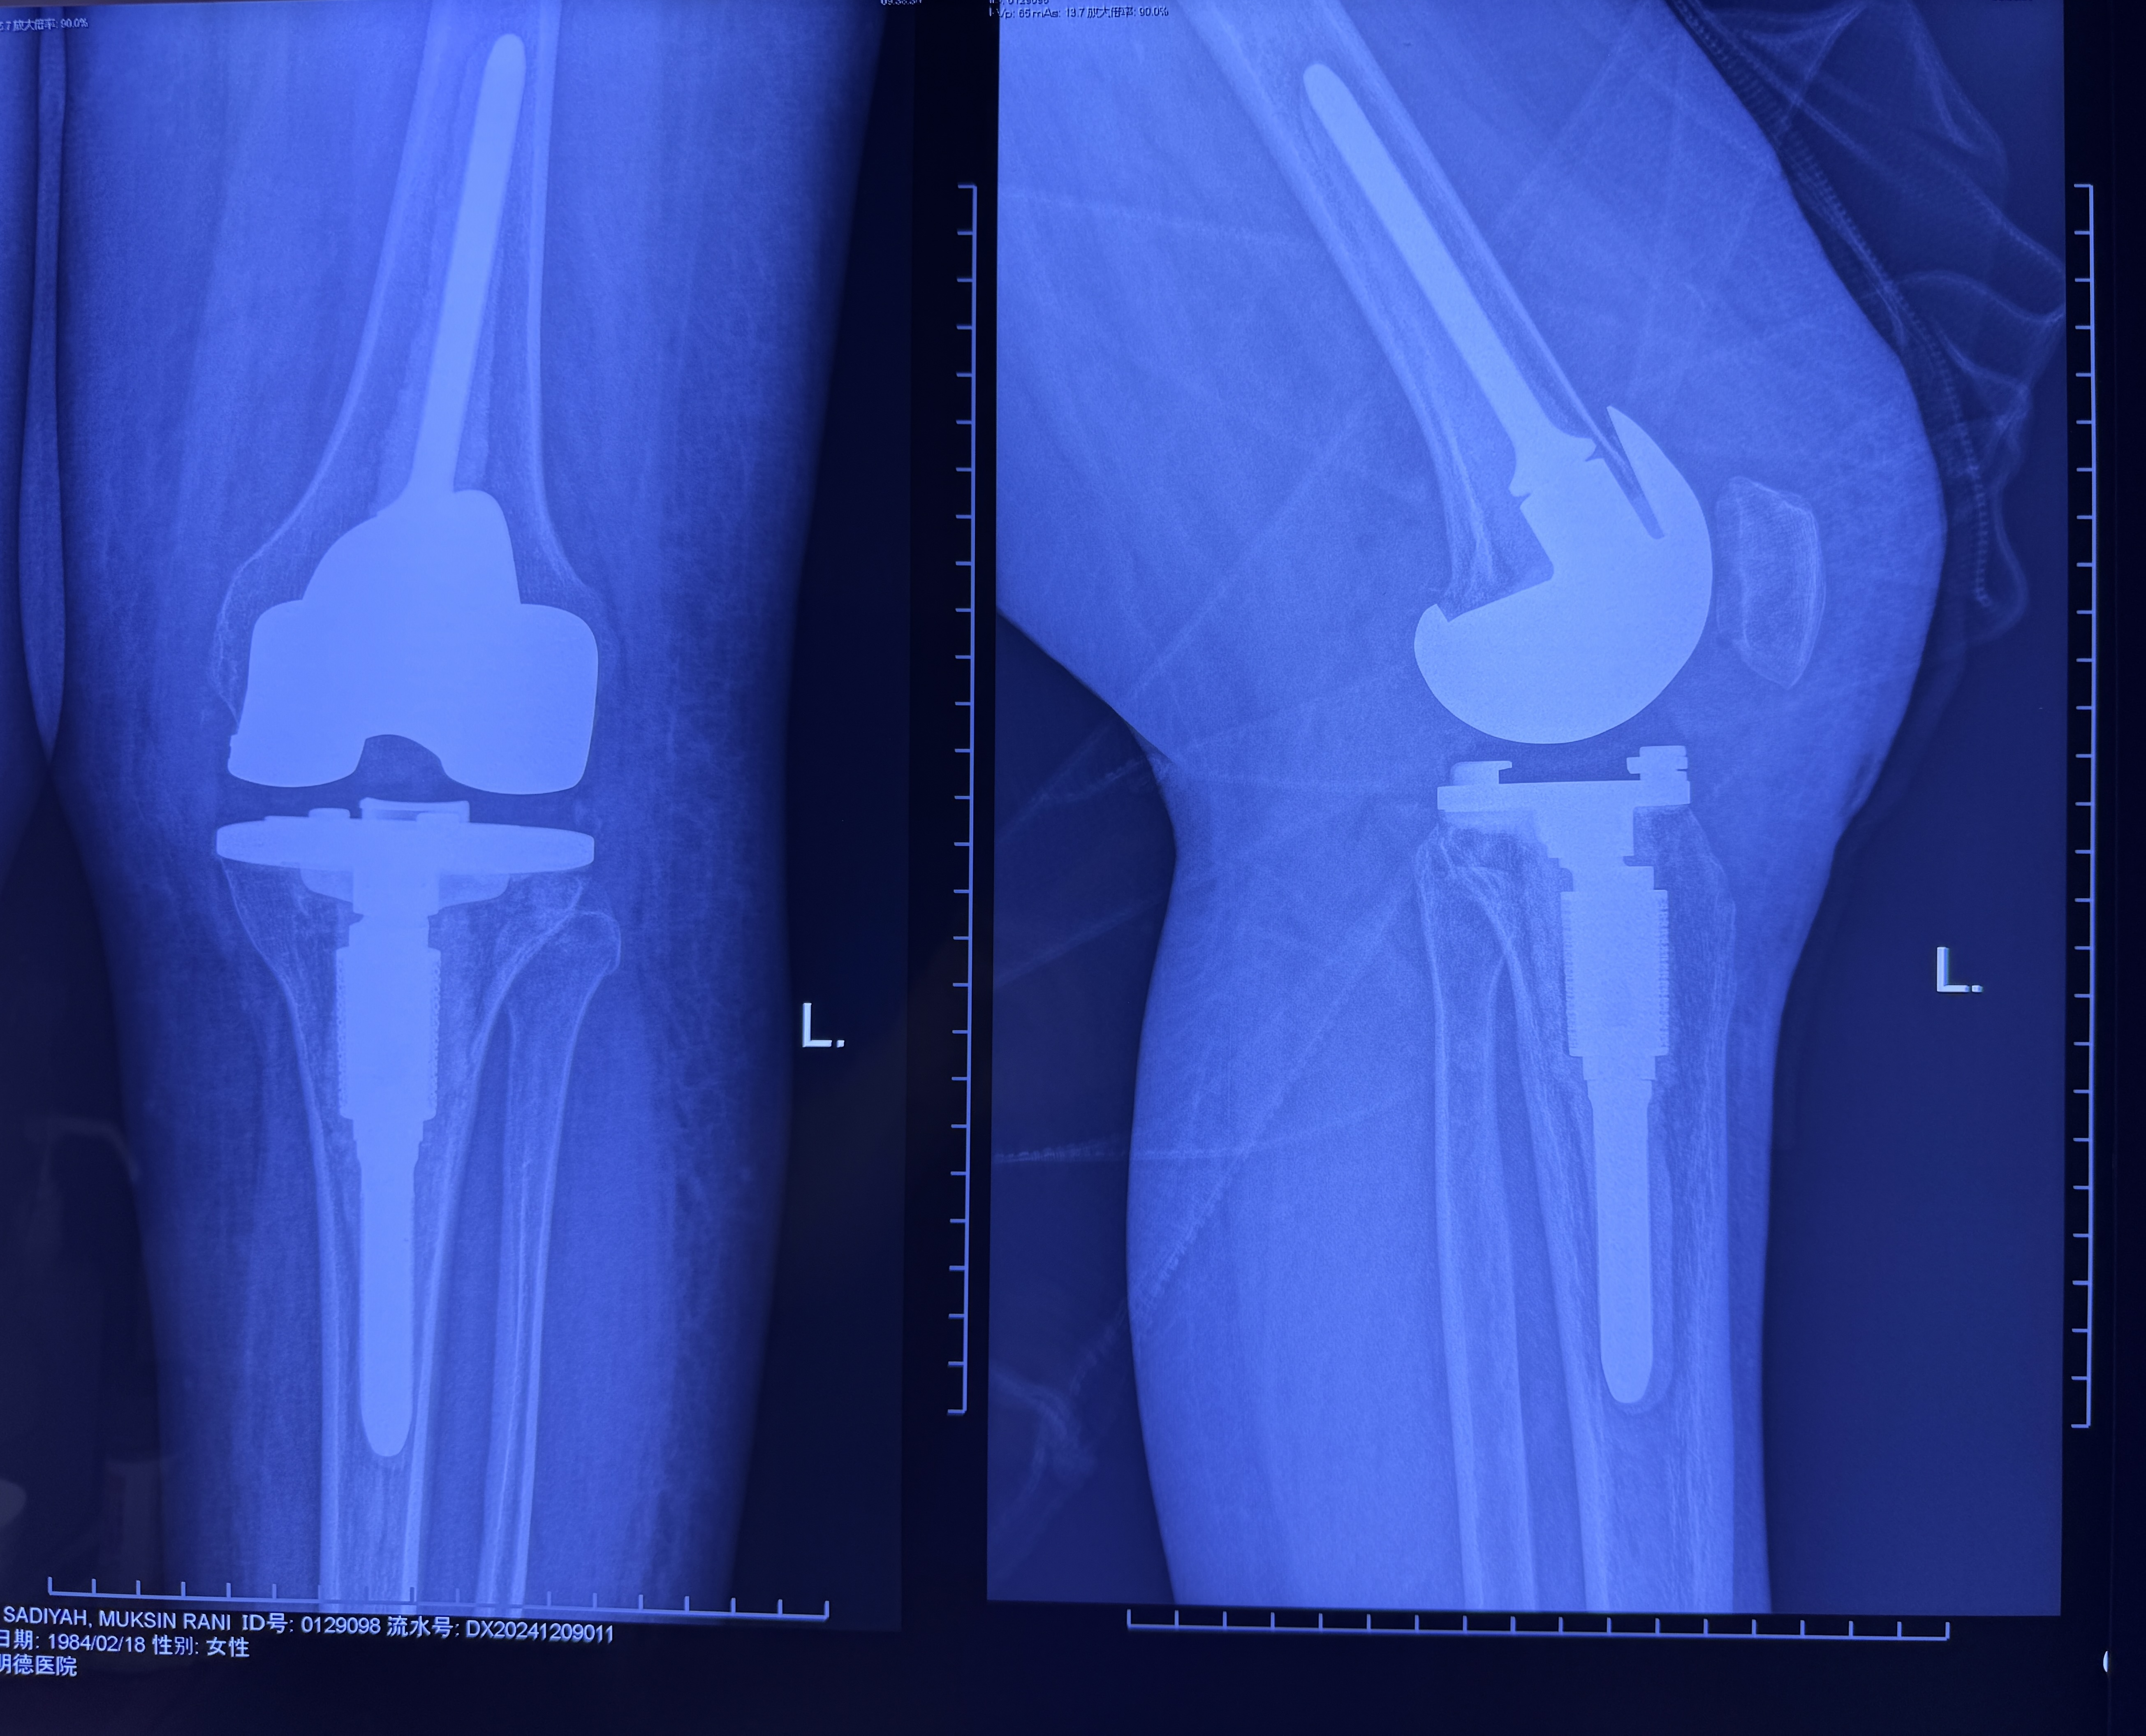

经多学科讨论认为,患者左膝关节的病变已处于晚期,病变滑膜的增生侵袭已经导致左膝关节的软骨、韧带以及部分软骨下骨结构的严重破坏。常规病灶清理手术恐难以实现彻底清除病变、修复骨缺损,从而难以恢复病膝的生理功能。膝关节置换可能是唯一的选择,但传统膝关节置换术式对于年轻患者的远期功能维护存在局限。周昊嵬主任团队经充分医患沟通后,决定采用加长杆的特殊假体进行关节功能重建。

经过充分的术前准备,很快按计划对患者实施了手术。手术中证实该患者左膝关节腔内存在弥漫性滑膜组织增生,呈典型铁锈色绒毛结节样改变,软骨面缺损达Ⅲ级,很多区域已经侵及软骨下骨,彻底清除病变组织后,采用加长柄假体完成膝关节置换。术后病理也排除了结核等感染性病变。

术后,康复团队立即介入跟进,开始指导患者床旁适应性训练。在手术后两周病人基本可以无辅助行走。术后三个月在康复训练的帮助下,左下肢肌肉张力几乎完全恢复,可以平稳行走。